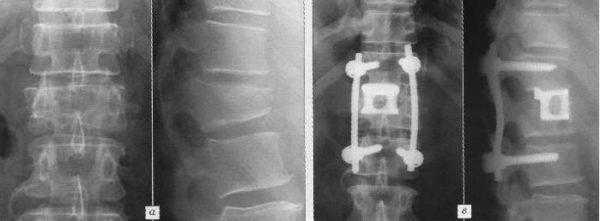

Но особенно результативным, по данным проведенных исследований, является межтеловой спондилодез. Поскольку тела позвонков значительно лучше снабжаются кровью, имеют большее количество клеточных элементов и отличаются высоким потенциалом к образованию новой костной ткани, имплантированные между ними объекты приживаются значительно лучше, чем установленные между отростками позвонков. При таком способе фиксации успешного спондилодеза удается добиться в 96% случаев. В противном случае позвонки могут не срастись, что приведет к сохранению болей в спине, а в дальнейшем к тяжелым последствиям.

Чтобы иммобилизация позвоночно-двигательного сегмента была максимально надежной, нередко операция дополняется выполнением транспедикулярной фиксации. В таком случае устанавливаются специальные металлические конструкции, которые еще более упрочняют скрепление тел позвонков.

Межтеловой кейдж для фиксации позвонков

Чтобы операция дала наилучший результат, часто используется межтеловой кейдж, который должен отвечать таким требованиям:

- обеспечивать стабильность тел позвонков;

- гарантировать сохранение нормальной высоты межпозвоночных дисков, что позволяет избежать компрессии нервов;

- быть изготовленным со специальным пространством через которое, можно вводить костный цемент, искусственную костнозамещающую крошку или препаратов увеличивающих рост костной ткани ;

- Корригировать и фиксировать боковой (сагиттальный) и передний (фронтальный) баланс позвоночника;

- Удерживать нагрузку которая ложиться на ось позвоночника.

Безусловно, предельно качественное выполнение ТПФ обеспечивается при применении устройств 3-го поколения. Современные имплантируемые кейджи позволяют надежно зафиксировать патологически измененный сегмент позвоночника и устранить болевой синдром, обусловленный его остаточной подвижностью.

Кейдж представляет собой полую конструкцию, подобранную по диаметр тела позвонка. Он устанавливается вместо удаляемого межпозвоночного диска и жестко фиксирует пространство между телами позвонков. Такой вид фиксации применяется при переломах позвоночника или при дегенеративно-деструктивных процессах, приводящих к полному или частичному разрушению межпозвоночных дисков.

Сам имплант изготовлен из титанового сплава или керамики, после установки его полость заполняется специальным цементом, сходным по структуре с костной тканью.

В реабилитационном периоде межпозвоночный кейдж и окружающая костная ткань взаимно прорастают друг в друга, обеспечивая, со временем, полное восстановление функции поврежденного сегмента позвоночника.